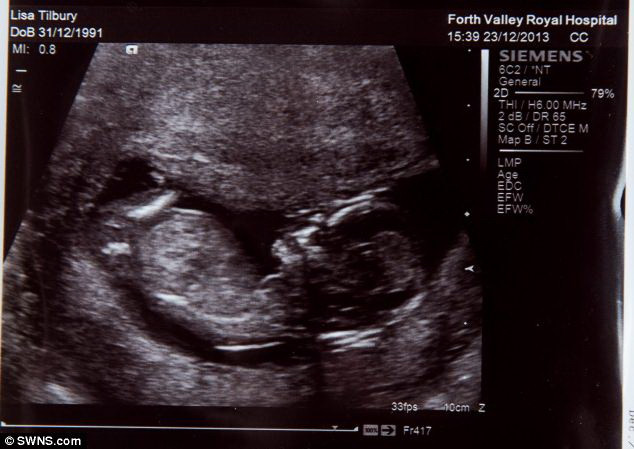

Quyết sinh con dù thai nhi chỉ có 1% cơ hội sống sót ảnh 2Ảnh chụp siêu âm cho biết thai nhi có một khối u. (Nguồn: Daily Mail)

Dù thai nhi đã 6 tháng tuổi, nhưng giới tính của thai vẫn chưa được xác định. Việc khối u là lành tính hay ác tính cũng chưa được làm rõ. Các bác sỹ nghi ngờ rằng đây có thể là neuroblastoma - một dạng ung thư phổ biến ở trẻ em.